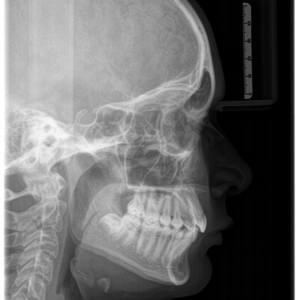

Radiografías

Periapicales, bitewing oclusales

Panorámicas y teleradiografías para ortodoncia

Scanner Cone-Beam CT de última generación